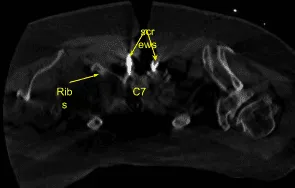

Image-guided stereotactic frame with neuronavigation techniques were used to place the instrumentation. We placed bilateral T1 pedicle screws and decorticated with electric high-speed drill cannulating with the navigated pedicle finder, palpating for breaches, measuring the depths, under tapping by 11 mm and placing 30 mm x 5.0 mm titanium pedicle screws bilaterally without difficulty.

Next, we placed bilateral lateral mass screws at C6. Inspecting the deformity of the spine, a decision was made not to place the C5 lateral mass screws because of kyphotic deformity and difficulty with rod placement.

So, we next decorticated the joints at C6-C7 and C7-T1 and bilateral T1 transverse processes with electric high-speed drill for the arthrodesis. The autograft resected was morselized. Precut-precontoured titanium rods were placed across the tulips from C6 to T1 and secured with locking caps and then final tightened with a torque and anti-torque device.